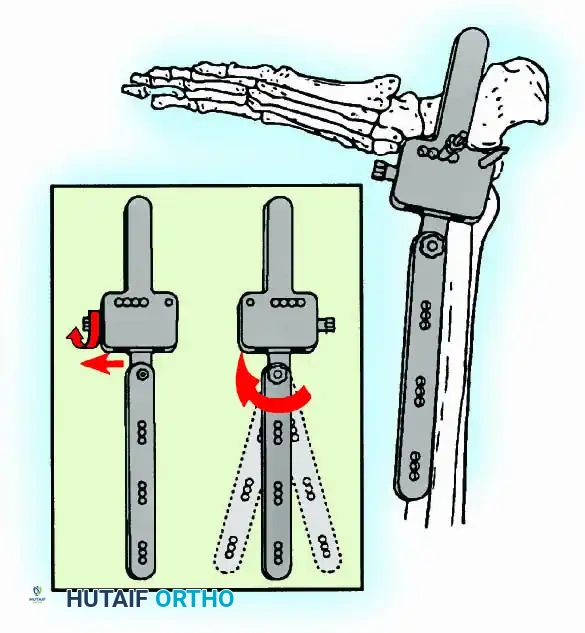

External Fixation

Historically pioneered by Charnley, external compression arthrodesis utilizes pins placed through the distal tibia and the body of the talus. Because Charnley's original uniplanar device lacked rotatory stability, Calandruccio designed a triangular frame to control motion in all three planes while applying massive compression.

Modern iterations, such as the Calandruccio II compression device, offer greater latitude in pin placement to avoid compromised skin. Ring or circular external fixators (Ilizarov, Taylor Spatial Frame) are the gold standard for salvage situations, including active infection, massive bone loss, or failed TAA, as they allow for simultaneous compression, deformity correction, and early weight-bearing.